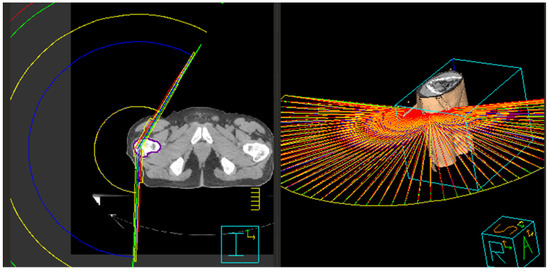

Figure 4.

Volumetric modulated arc therapy treatment technique illustrated in (left) two dimensions and (right) three dimensions. Note the sweeping, continuous arc motion around the patient.